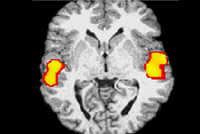

Ενεργοποίηση του εγκεφάλου κατά τη διάρκεια εφαρμογής αγωγής Ρεφλεξολογίας.

Στην παραπάνω απεικόνιση καταγράφεται η νευρωνική δραστηριότητα στον εγκέφαλο, όπως προκύπτει μέσω της σχετικά πρόσφατης μεθόδου νευροαπεικόνισης που ονομάζεται 'Λειτουργική Απεικόνιση Μαγνητικού Συντονισμού' (ΛΑΜΣ, fMRI) [2].

2. Nakamaru T, Miura N, Ushima A, Kawashima R., Τμήμα Λειτουργικών Απεικονίσεων του Εγκεφάλου, της Ιατρικής Σχολής του Πανεπιστημίου Tohoku, του Sendai της Ιαπωνίας.